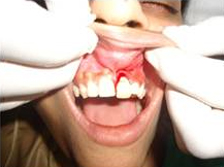

Pre Operation

Single Tooth Implant

Drilled socket for Implant